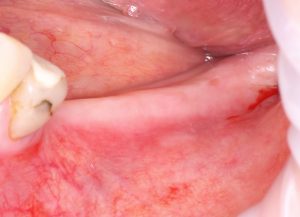

Осталось только наложить швы:

и подождать 3-4 месяца до интеграции имплантов.

Посмотрим на результат:

особенно на то, что внутри:

Обратите внимание, что между пересаженным костным блоком и принимающим ложем нет чёткой границы, а сам регенерат по цвету и структура, практически, не отличается от альвеолярного гребня. Это как раз то, что я называю хорошим результатом остеопластической операции. Нам останется только сформировать десну и установить коронки на интегрированные имплантаты.